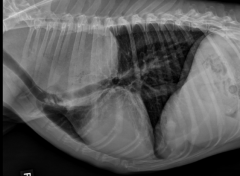

The caudal boarder of the cardiac silhouette may be adjacent to or superimposed over the diaphragm, depending on the _____ of _____.

Describe the difference b/t expiration and hyperinflation views.

phase of respiration (greater overlap during expiration)

During expiration, caridac silhouette appears larger in relation to size of thoracic cavity (increased cardiac-to-thoracic ratio), with greater sternal contact and more dorsal positioning of the trachea.

Hyperinflation of lungs creates a larger thoracic cavity and a smaller- appearing cardiac silhouette (decreased cardiac-to-thoracic ratio)